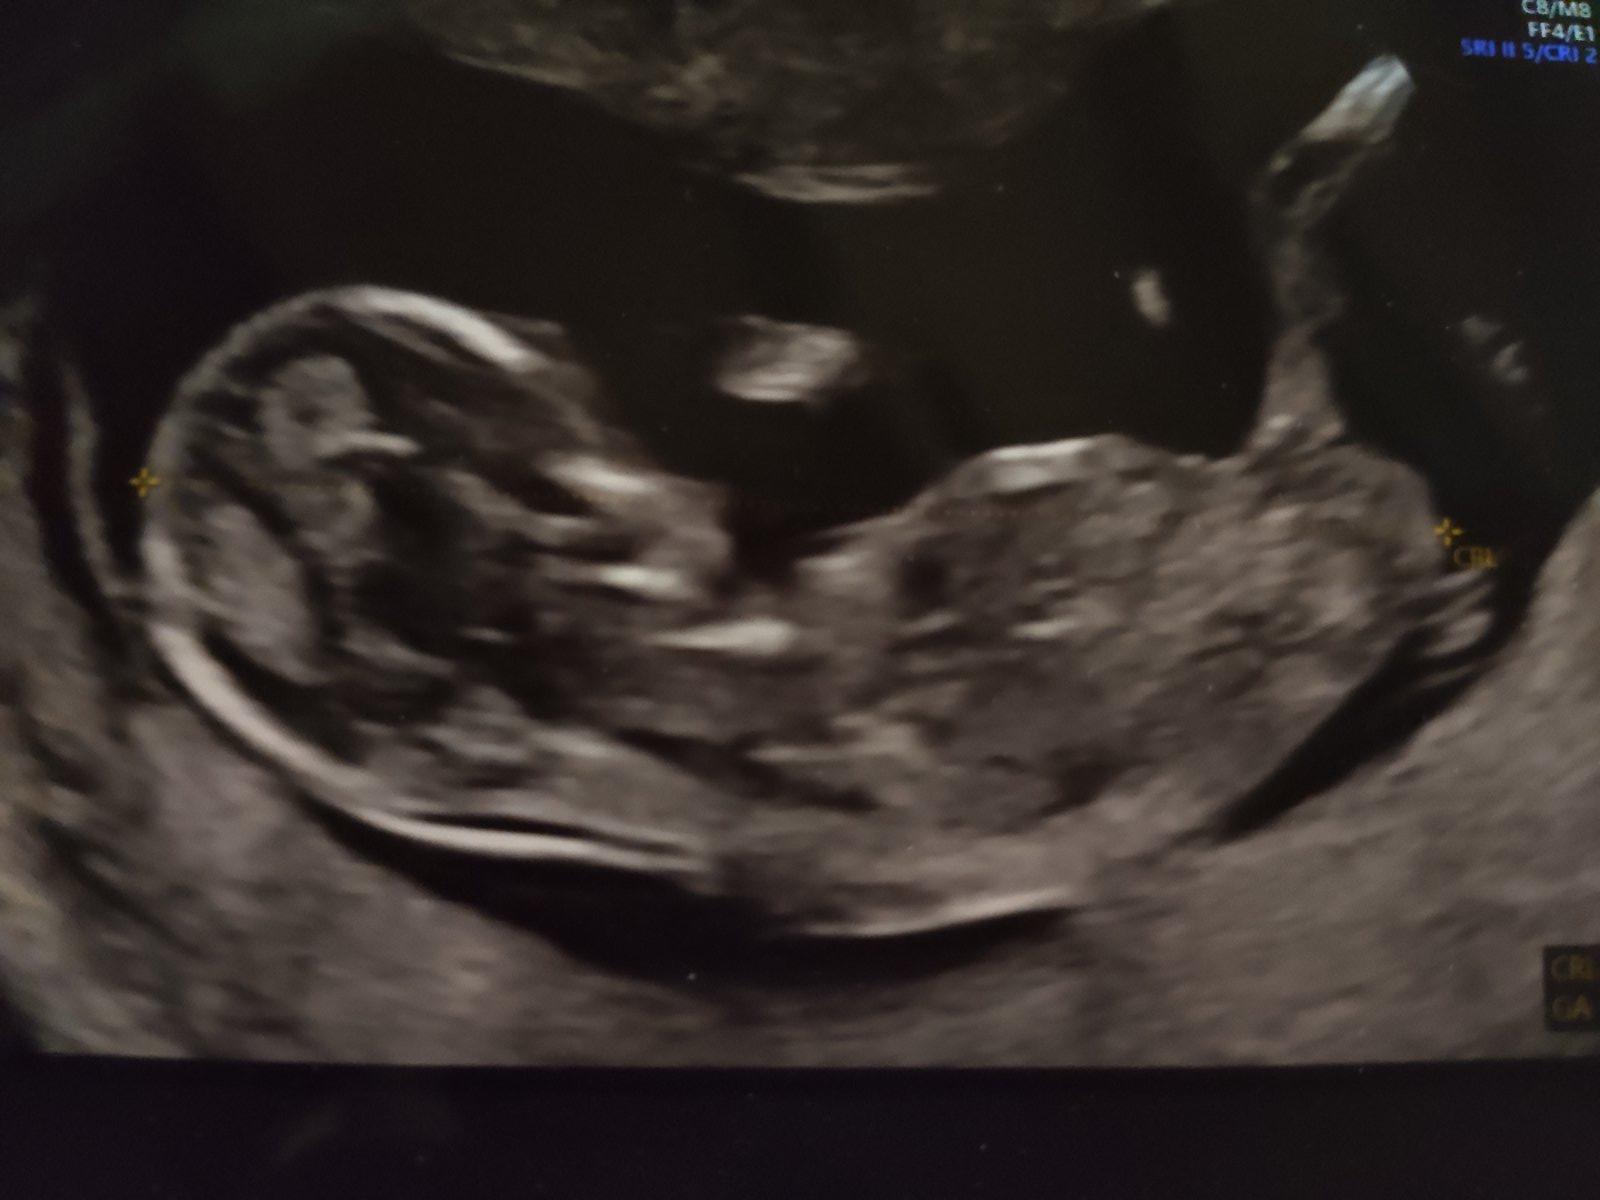

@flowerkacrochet 3D nemám, iba tvaricku. Úprimne o nič mi neide, len možno niekto z tohto obrázka prečíta viac ako ja 😄 už by som si chcela pomaly kupovať vybavicku, ale teda neviem ktorým smerom. Túto foto mám z 13 týždňa, ale teda ja ani tam pohlavie nevidím 😄

Lékař nám ve 13 tt říkal, že pravděpodobnost, že určí pohlaví správně, je v tomto týdnu těhotenství 50%.